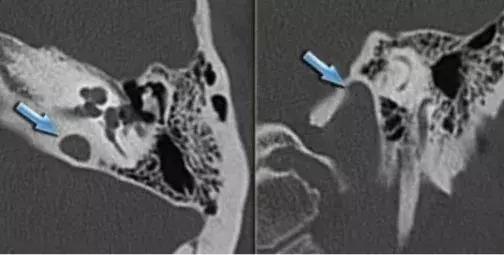

解剖变异的患者大多数没有临床症状,最常见为听力降落和搏动性耳鸣,其次是眩晕和出血。

除了以上这三种颈内动脉异位、颈内动脉外位、颈静脉球高位以外,还有乳突导血管异常、上半规管骨裂和后半规管骨裂。